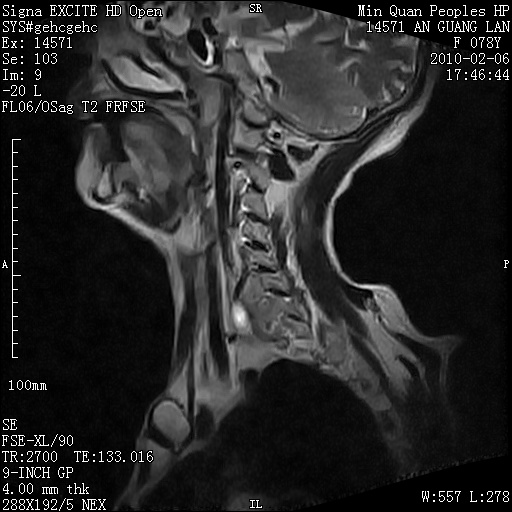

标题: MRI2763:C6、C7椎体病变性质?

f,78y,颈部与双上肢阵发性剧痛40余天。ct可见c6、c7椎体虫蚀样破坏,其间椎间隙变窄(没有图片资料可供上传)。

考虑椎体结核并椎旁脓肿。

支持 c6、7椎体结核并椎旁冷脓肿形成。

考虑:c6/7椎体结核并椎旁脓肿形成,建议增强扫描。